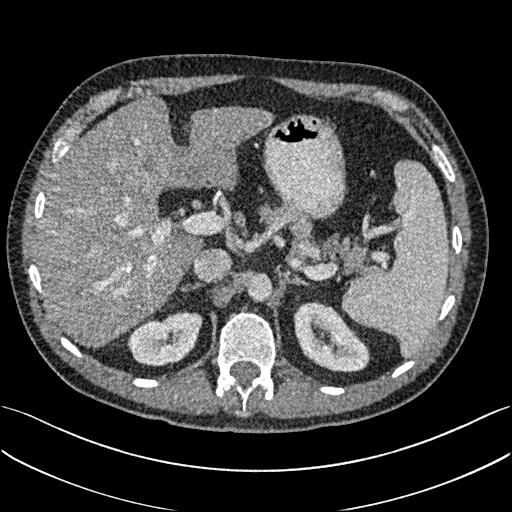

To show the denoising effect of the selected networks, we took two representative slices as shown in Figs. 5 and 7. And Figs. 6 and 8 are the zoomed regions-of-interest (ROIs) marked by the red rectangles in Figs. 5 and 7. All the networks demonstrated certain denoising capabilities. However, CNN-MSE blurred the images and introduced waxy artifacts as expected, which are easily observed in the zoomed ROIs in Figs. 6e and 8e. WGAN-MSE was able to improve the result of CNN-MSE by avoiding over-smooth but minor streak artifacts can still be observed especially compared to CNN-VGG and WGAN-VGG. Meanwhile, using WGAN or GAN alone generated stronger noise (Figs. 6g and 8g) than the other networks enhanced a few white structures in the WGAN/GAN generated images, which are originated from the low dose streak artifact in LDCT images, while on the contrary the CNN-VGG and WGAN-VGG images are visually more similar to the NDCT images. This is because the VGG loss used in CNN-VGG and WGAN-VGG is computed in a feature space that is trained previously on a very large natural image dataset [48]. By using VGG loss, we transferred the knowledge of human perception that is embedded in VGG network to CT image quality evaluation. The performance of using WGAN or GAN alone is not acceptable because it only maps the data distribution from LDCT to NDCT but does not guarantee the image content correspondence. As for the lesion detection in these two slices, all the networks enhance the lesion visibility compared to the original noisy low dose FBP images as noise is reduced by the different approaches.

As for iterative reconstruction technique, the reconstruction results depend greatly on the choices of the regularization parameters. The implemented dictionary learning reconstruction (DictRecon) result gave the most aggressive noise reduction effect compared to the network outputs as a result of strong regularization. However, it over-smoothed some fine structures. For example, in Fig. 8, the vessel pointed by the green arrow was smeared out while it is easily identifiable in NDCT as well as WGAN-VGG images. Yet, as an iterative reconstruction method, DictRecon has its advantage over post-processing method. As pointed by the red arrow in Fig 8, there is a bright spot which can be seen in DictRecon and NDCT images, but is not observable in LDCT and network processed images. Since the WGAN-VGG image is generated from LDCT image, in which this bright spot is not easily observed, it is reasonable that we do not see the bright spot in the images processed by neural networks. In other words, we do not want the network to generate structure that does not exist in the original images. In short, the proposed WGAN-VGG network is a post-processing method and information that is lost during the FBP reconstruction cannot easily be recovered, which is one limitation for all the post-processing methods. On the other hand, as an iterative reconstruction method, DictRecon algorithm generates images from raw data, which has more information than the post-processing methods.